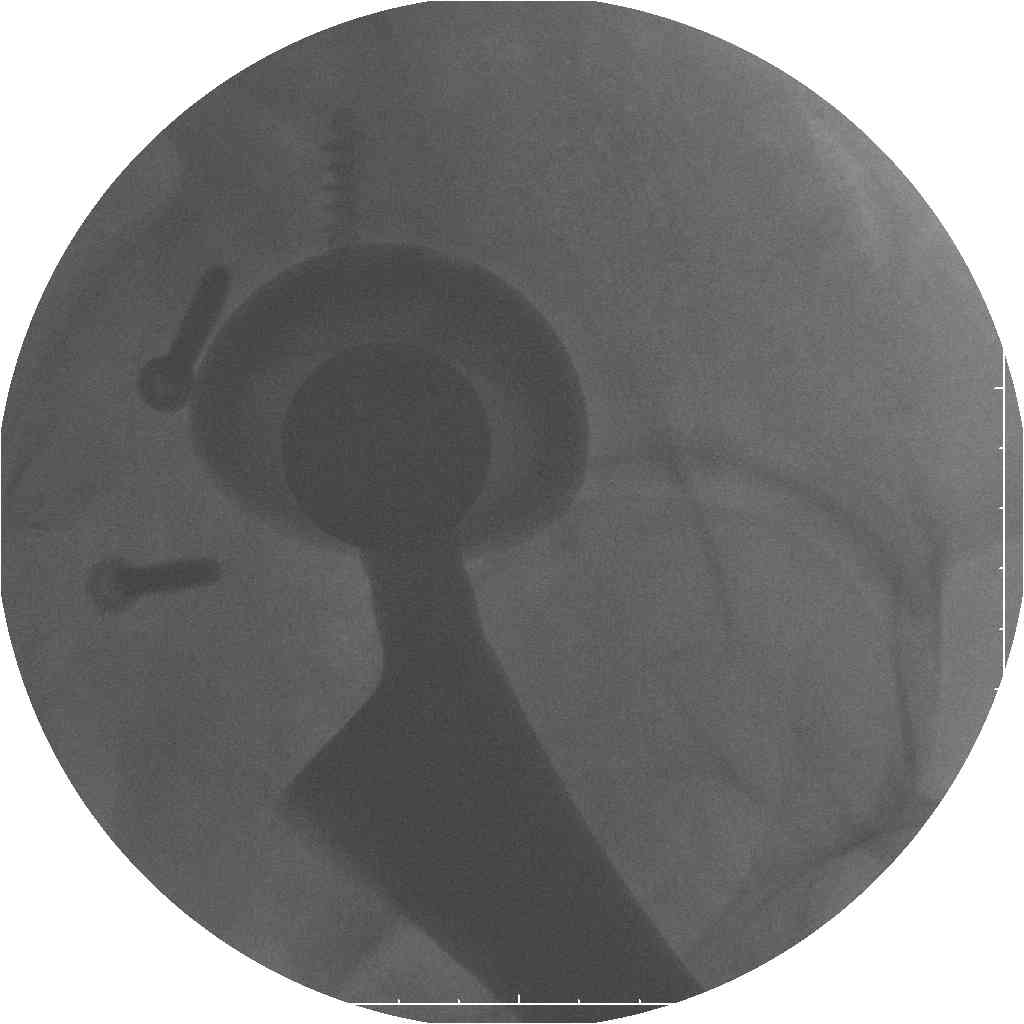

Уважаемые коллеги.В 3 Центральный Военный Клинический Госпиталь имени А. А. Вишневского, что в Красногорске, Московской области, в отделение эндопротезирования крупных суставов поступил пациент 1960 года рождения Жалобы при поступлении: на боли в области левого тазобедренного сустава (больной указывает на точку расположенная в середине условной линии между седалищным бугром и большим вертелом), усиливающиеся в начале ходьбы, при опоре на левую ногу с иррадиацией болей по наружной и наружно-задней поверхности левого бедра, левый коленный сустав; снижение объема движения в левом тазобедренном суставе, снижение опорной способности левой нижней конечности, хромоту на левую ногу, необходимость использования дополнительной опоры (костыли) при ходьбе, снижение объема двигательной активности из за болей в суставе.В анамнезе: Со слов больного, согласно медицинских документов, в 1989 году получил травму левой нижней конечности: закрытый перелом левой вертлужной впадины с центральным вывихом головки левой бедренной кости. Лечился консервативное. В процессе лечения сформировался посттравматический артроз, укорочение левой нижней конечности до 5 см. 25.04.2005 года в Подольском Окружном Госпитале Министерства Обороны выполнено: одномоменто, остеосинтез заднего края вертлужной впадины фрагментом резецированной головки бедренной кости и тотальное эндопротезирование левого тазобедренного сустава бесцементным эндопротезом "VERSIS ET" с бесцементной чашкой TRILOGY. Послеоперационный период осложнился ранним нагноением области эндопротеза, в результате санаций очага инфекции и антибиотикотерапии, активного промывного дренирования антисептиками, послеоперационная рана зажила. После операции, со слов больного, через два месяца в полном объеме стал нагружать левую нижнюю конечность. В течение полгода, после операции чувствовал себя вполне удовлетворительно. С марта 2006года стал отмечать появление болей в области тазобедренного сустава, то в области паха, то в области левой ягодицы. С августа месяца отмечает те жалобы, с которыми он сейчас к нам обратился. Температура тела, после заживления раны, нормальная. В анализах крови, лейкоциты около 7 тыс, формула нормальная, СОЭ 12 мм ч. Локально: при осмотре обеих нижних конечностей, анатомическая ось конечности не нарушена; отмечено относительное укорочение левой н\конечности на 1.5 см., гипотрофия мышц левого бедра 3 см, голени 2 см, симптом. Объем движений в тазобедренных суставах: правый~ сгибание- 60 гр, разгибание-180 гр ,отведение- 35 гр, левый~ сгибание- 110 гр , разгибание-170 гр , отведение-15 гр. Контуры других суставов н/конечностей обычные, объем движений в них не страдает. Пульсация на артериях конечностей удовлетворительная. Неврологические нарушения конечностей отсутствуют, рефлексы на обеих н/конечностях одинаковые, чувствительных нарушений нет. Осевая нагрузка на левую нижнюю конечность вызывает боль в точке расположенная в середине условной линии между седалищным бугром и большим вертелом. Отмечается пигментация и пастозность нижней трети обеих голеней и стоп, характерная для посттромботической болезни. На Цветном дуплексном сканировании сосудов нижних конечностей: Нестенозирующий атеросклероз обеих бедренных и подколенных артерий . Гемодинамически значимых препятствий кровотоку в магистральных артериях ног не выявлено. Глубокие и поверхностные вены нижних конечностей проходимы. Умеренная недостаточность клапанов подколенных вен. Данных за тромбоз глубоких вен на момент осмотра не получено.А вот что пишет наш рентгенолог: На серии рентгенограмм области левого тазобедренного сустава определяется тотальный бесцементный эндопротез. Вокруг тени чашки эндопротеза определяется ободок остеорезорбции. Кроме того, визуализируется деформированный костный винт фиксирующий консолидированный отломок вертлужной впадины, вплотную прилегающий к тени чашки эндопротеза. Заключение: Рентгеновские признаки нестабильности чашки тотального эндопротеза. Лучевая нагрузка: 6 мЗв. У нас в отделении разошлись мнения: начальник мой утверждает, после сравнения снимков, принесенных больным от августа и октября 2006года и наших рентгенснимков, что у больного нет нестабильности вертлужного компонента, и что надо назначит курс консервативной терапии: препараты кальция, миакальцик, увеличить осевую нагрузку на левую нижнюю конечность, ЛФК направления на укрепление мышц бедра, ягодиц, физиолечение. А я утверждаю, что у больного клиника нестабильности вертлужного компонента, и необходима ревизия вертлужного компонента, не исключено даже наличие инфекции под чашкой эндопротеза (не смотря на отсутствие клинических признаков инфекции). В результате проводимой консервативной терапии, боли у больного усилились. Помогите рассудить нас, мы готовы выслушать ваши мнения по этому поводу. С уважением Батал Шушания.3 ЦВКГ имени А. А. Вишневского

Ув. Коллега.Четких рентгенологических признаков нестабильности вертлужного компонента действительно нет. Здесь, кроме нестабильности, можно искать причину в поясничный отдел позвоночника(Hip-spain синдром - всё-таки 15 лет ходил с укорочением),либо сделать спиральный КТ и посмотреть, нет ли несращения в области старого перлома вертлужной впадины. Зачастую ложные суставы подвздошной, седалищной, а иногда и лонной костей являются причинами несостоятельности эндопротезов.

поясничного отдела позвоночника. Есть зона остеолиза вокруг чашки, но как правило, дополнительный винт держит чашку достаточно хорошо, и даже при наличии микроподвижности, это не сопровождается столь ярким болевым синдромом. Поэтому, я бы сделал следующее: МРТ позвоночника, пункцию ТБС для исключения инфекционного процесса. Ревизию рассматривал бы как крайний вариант, учитывая выполненную костную пластику и отсутствие явных признаков нестабильности.

уважаемый коллега, Антон Вакуленко. Спасибо за четкий, расписанный по пунктам план действий. При поступлении пациента в отделение, я думал точно как вы. Но на следующий день, выполнил многопроеционное рентгенисследование, показал невропатологу, и доложил начальнику отделения о больном.После разбора пришли к следующему, да у больного действительно нестабильность вертлужного компонента, есть зона лизиса в месте костного аутотрансплантата, а в месте фиксаци чашки деротационным винтом четко выраженный контакт чашки с костной тканю. Мы пришли к выводу,что лизис костного аутотрансплантата из за осевой перегрузки на фоне незавершенного ремоделирования (вес больного 130 кг). Потому мы и приняли план вышеуказанного лечения. Провели беседу с больным, больной согласился с нами. Через 3-6 месяцев мы оценим эффективность лечения и доложу. Возможно и придется тогда идти на ревизию с заменой только вертлужного компонента а может и придется удалить весь эндопротез с установкой спейсера.. посмотрим.....